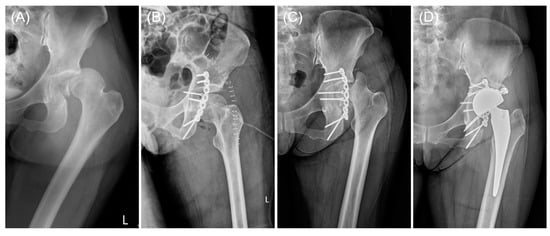

2.3. Implant Design